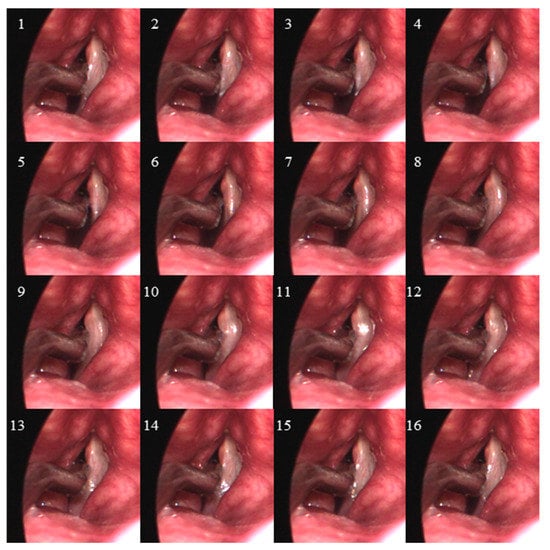

A 78-year-old male was recruited for this study who had previously (12 years prior) undergone a unilateral, right vocal fold hemilaryngectomy for the treatment of laryngeal cancer (T2bN0M0 squamous cell carcinoma). An adipose tissue implant, taken from the periumbilical region, was injected to medialize the right vocal fold and facilitate glottal closure as the left vocal fold oscillated during phonation. The individual follows up regularly with his treating laryngologist for cancer surveillance and to assess vocal function, which includes laryngeal videoendoscopic examinations with stroboscopy. Figure 1 displays endoscopic images of the individual’s larynx in an abducted and adducted state. Video S1 (Supplementary Materials) displays a segment from the videostroboscopic examination as the individual produces voice at a comfortable and higher-than-comfortable pitch level. According to clinical notes, the individual exhibited normal pliability and mucosal wave of the left vocal fold and diminished pliability and mucosal wave of the right vocal fold, consistent with expectations following the hemilaryngectomy and reconstruction. Complete glottal closure was observed during phonation with entrained vocal fold oscillation, mild phase asymmetry, and significantly reduced amplitude of the right vocal fold. There was no evidence of recurrent laryngeal disease.

Figure 1. Endoscopic images of the larynx from the videostroboscopy examination of the participant who had previously undergone a unilateral (right vocal fold) hemilaryngectomy to treat laryngeal cancer. Shown are snapshots of the vocal folds in states of (a) abduction and (b) adduction.

Endoscopic visualization of the larynx during sustained phonation at comfortable pitch and loudness levels allowed the endoscopist to place the dual-sensor pressure probe such that the proximal sensor was positioned intraglottally and the distal sensor subglottally. The clinician held a left-handed ISP probe with pressure-sensing elements facing the functioning left vocal fold of the participant. As recommended in prior work [], it was necessary to ask the subject to produce sustained phonation while the ISP probe was slowly swept in the superior–inferior dimension. Then, during the data analysis phase, features related to vocal fold collision were then identified to determine when adequate vocal fold contact occurred to capture peak collision pressures. Figure 3 displays high-speed videoendoscopic images from one phonatory cycle during which the proximal pressure sensor of the ISP probe was deemed to be positioned in the strike zone of vocal fold collision. Video S2 (Supplementary Materials) shows the corresponding high-speed videoendoscopy data for this phonatory segment.

Figure 3. One phonatory cycle is displayed from the high-speed videoendoscopy data (2000 frames per second) during which the intraglottal pressure sensor of the ISP probe was deemed to be in the strike zone of the left vocal fold. Sixteen frames (frame indices indicated) are shown for the phonatory cycle that was 8 ms in duration, translating to a fundamental frequency of tissue oscillation of 125 Hz.

4.4. Study Limitations